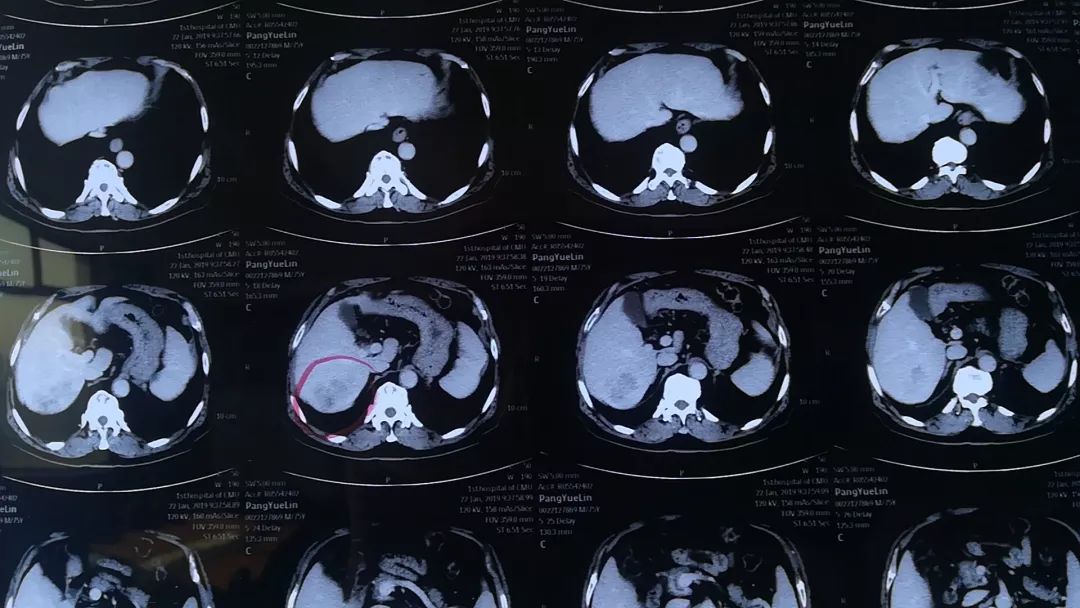

男性患者,75岁,三个月前体检时发现甲胎蛋白增高,完善肝部超声后提示肝肿物。先后就诊于省内知名三甲医院及我院行上腹部CT、磁共振检查后诊断为“肝占位,考虑肝癌”,需要手术治疗。

2月15日下午,林杰主任和蔡相军主任一同为该患者在全麻下行肝S7段切除术。